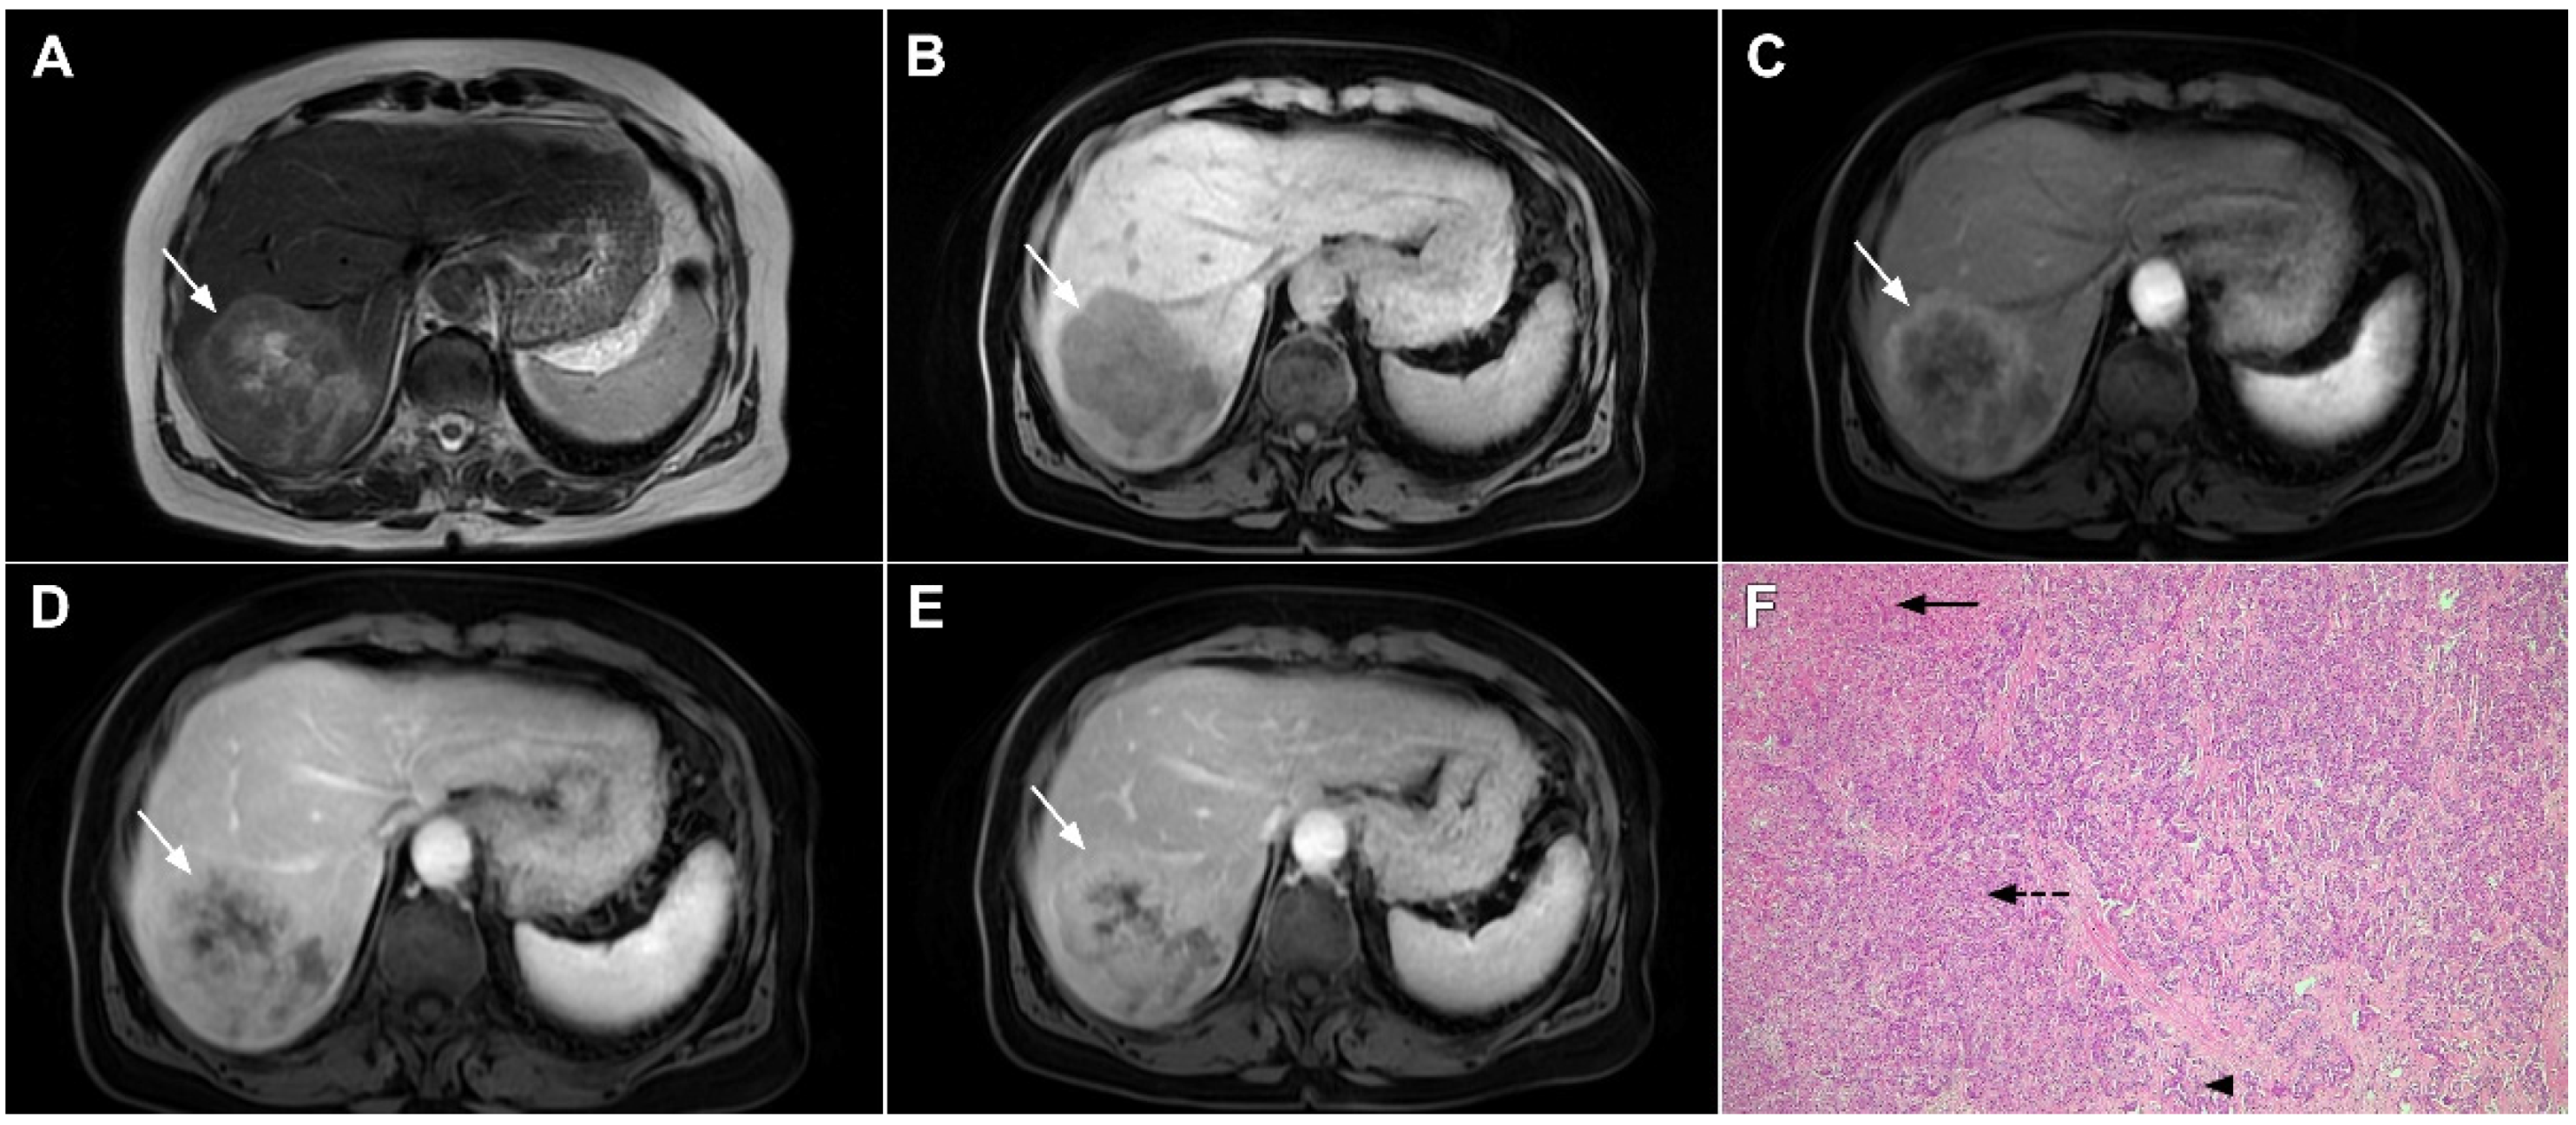

3.1.5. Liver Echinococcosis

- Eckert, J.; Conraths, F.J.; Tackmann, K. Echinococcosis: An emerging or re-emerging zoonosis? Int. J. Parasitol. 2000, 30, 1283–1294. [Google Scholar] [CrossRef]

- Pedrosa, I.; Saíz, A.; Arrazola, J.; Ferreirós, J.; Pedrosa, C.S. Hydatid disease: Radiologic and pathologic features and complications. Radiographics 2000, 20, 795–817. [Google Scholar] [CrossRef] [PubMed]

- Pohnan, R.; Ryska, M.; Hytych, V.; Matej, R.; Hrabal, P.; Pudil, J. Echinococcosis mimicking liver malignancy: A case report. Int. J. Surg. Case Rep. 2017, 36, 55–58. [Google Scholar] [CrossRef] [PubMed]

- Wa, Z.C.; Du, T.; Li, X.F.; Xu, H.Q.; Suo-Ang, Q.C.; Chen, L.D.; Hu, H.T.; Wang, W.; Lu, M.D. Differential diagnosis between hepatic alveolar echinococcosis and intrahepatic cholangiocarcinoma with conventional ultrasound and contrast-enhanced ultrasound. BMC Med. Imaging 2020, 20, 101. [Google Scholar] [CrossRef] [PubMed]

- Kantarci, M.; Bayraktutan, U.; Karabulut, N.; Aydinli, B.; Ogul, H.; Yuce, I.; Calik, M.; Eren, S.; Atamanalp, S.S.; Oto, A. Alveolar echinococcosis: Spectrum of findings at cross-sectional imaging. Radiographics 2012, 32, 2053–2070. [Google Scholar] [CrossRef] [PubMed]

- Kodama, Y.; Fujita, N.; Shimizu, T.; Endo, H.; Nambu, T.; Sato, N.; Todo, S.; Miyasaka, K. Alveolar echi-nococcosis: MR findings in the liver. Radiology 2003, 228, 172–177. [Google Scholar] [CrossRef] [PubMed]

- Mueller, J.; Stojkovic, M.; Berger, A.K.; Rosenberger, K.D.; Schlett, C.L.; Kauczor, H.U.; Junghanss, T.; Weber, T.F. How to not miss alveolar echinococcosis in hepatic lesions suspicious for cholangiocellular carcinoma. Abdom. Radiol. 2016, 41, 221–230. [Google Scholar] [CrossRef] [PubMed]

- Balci, N.C.; Tunaci, A.; Semelka, R.C.; Tunaci, M.; Ozden, I.; Rozanes, I.; Acunas, B. Hepatic alveolar echinococcosis: MRI findings. Magn. Reson. Imaging 2000, 18, 537–541. [Google Scholar] [CrossRef]